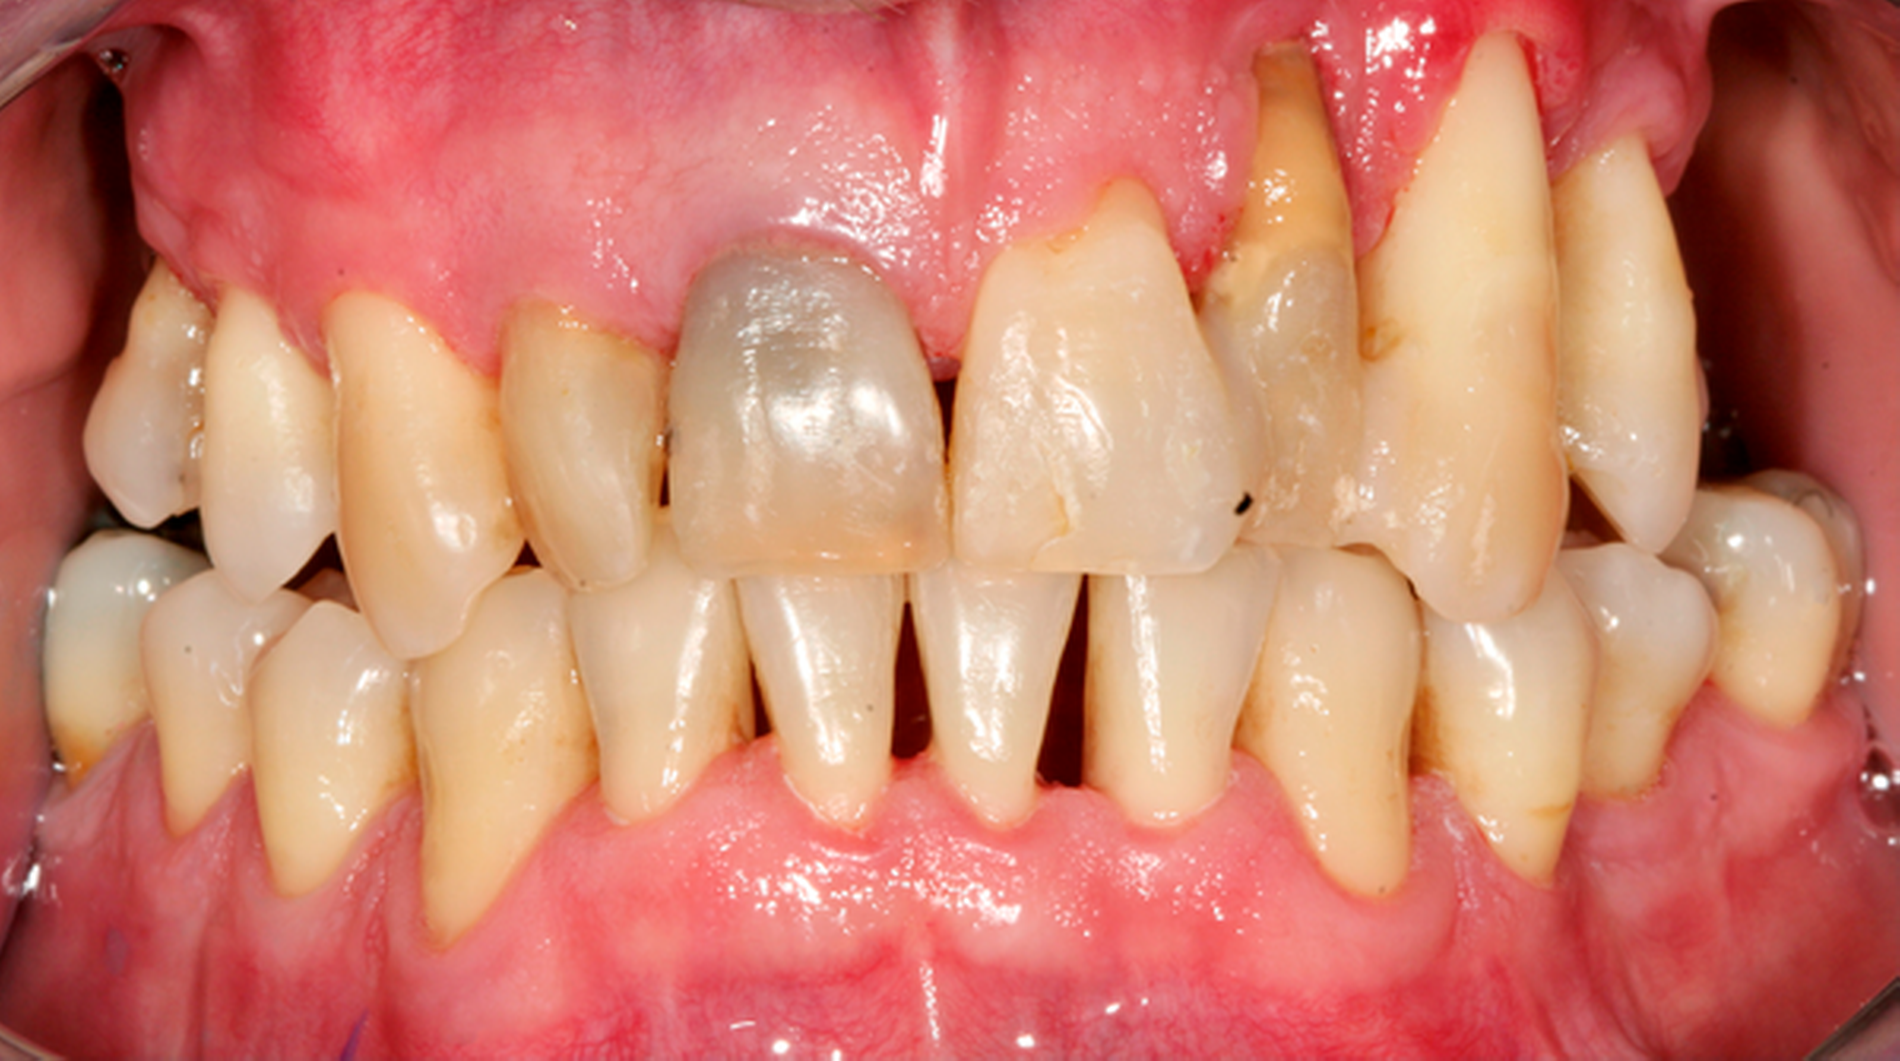

Abb. 2: Professionelle mechanische Plaquereduktion während einer UPT-Sitzung bei einem 50-jährigen Patienten mit reduziertem, aber gesundem Parodont im dritten Jahr nach zweiter Therapiestufe:

Weiterhin sollte bei der Betrachtung der Empfehlungen zu adjuvanten Maßnahmen zur PMPR – wie der antimikrobiellen Photodynamischen Therapie (aPDT) oder alternativer Verfahren wie der Er:Yag-Laseranwendung – beachtet werden, dass sich in der zugrunde liegenden systematischen Analyse von klinischen Studien von Trombelli et al. für diese Verfahren keine größeren klinischen Effekte nachweisen ließen [Trombelli et al., 2020].